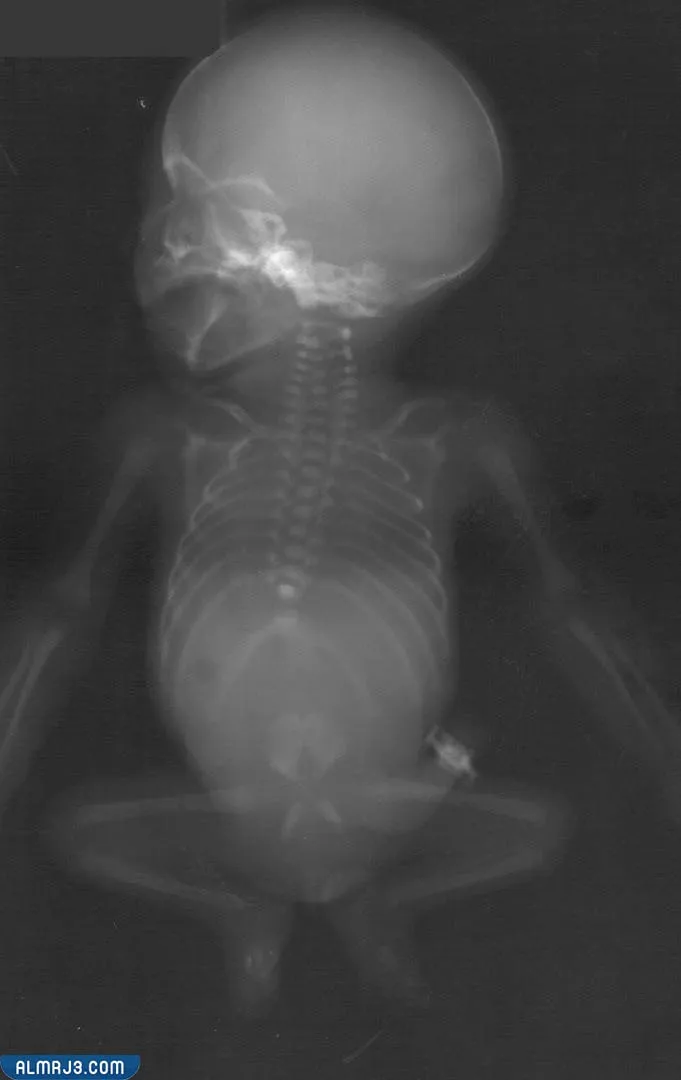

إنّ متلازمة التّراجع الذّيلي واحدة من الأمراض الخلقيّة النّادرة. حيثُ يصيب الأجزاء السّفليّة من جسد الإنسان، مسبّبةً انسداد فتحة الشّرج وتشوّه الأعضاء التناسليّة وكذلك البوليّة. وأحياناً قد تصل نتائج هذا المرض إلى حدوث اضطرابات شديدة في الجهاز الهضمي ووظيفته. ويبدأ المرض عند الإنسان منذ وجوده جنيناً في بطن أمّه، وذلك نتيجة لمجموعة من العوامل الوراثيّة والبيئيّة، بالإضافة إلى الظروف الصحيّة التّي تتعرّض لها الأم.[1]

- انعدام لعظام الذّيل في العمود الفقاري.

- ضمور الحوض والفقرات السفلية من العمود الفقاري.

- تشوهات كبيرة في القفص الصدري.